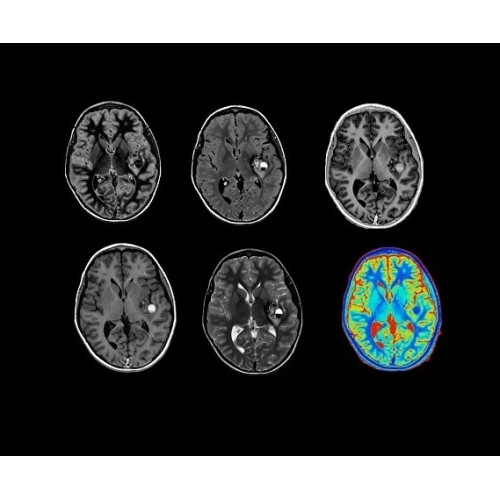

SIGNA Architect 3.0T — это новейший МРТ аппарат компании GE, который предлагает высочайший уровень производительности — в системе 128 приемных каналов, 48 канальная катушка головы, полный спектр клинических возможностей. Высокий уровень комфорта пациента обеспечивают такие особенности как отсоединяемый стол, положение пациента «ногами вперед» для всех видов исследований, SilentWorks — бесшумное и MAGIC — быстрое сканирование.

Теперь возможности МРТ поражают еще больше благодаря ультрасовременным решениям для визуализации с SIGNA Architect 3.0 Тл, объединяющей новейшие достижения в области МР-технологий и интуитивно понятный интерфейс. Система SIGNA Architect, разработанная на базе новой платформы SIGNA Works, представляет собой гармоничное сочетание дизайна и функциональности. Каждый элемент системы направлен на повышение производительности, эффективности клинической практики, финансовых показателей, а также комфорта и безопасности пациента.

Стандартный пакет приложений SIGNA Works позволит вам достичь желаемых результатов в клинической практике благодаря набору высокоэффективных средств визуализации. Программные приложения, входящие в состав данных клинических пакетов, включают широкий спектр контрастов, функции обработки 2D- и 3D-данных, а также возможность коррекции артефактов движения. SIGNA Works предоставляет набор инструментов, необходимых для проведения эффективного клинического исследования.

• NeuroWorks — универсальное решение для визуализации анатомии головного мозга, позвоночника, сосудов и периферических нервов с четкой дифференциацией тканей.

• ImageWorks — повысит производительность МРТ благодаря визуализации высокого качества с MAGIC, четкими результатами пост-процессинга с READYView.

• 48-канальная катушка TDI для головы, входящая в базовую комплектацию SIGNA Architect, обеспечивает феноменальную производительность с учетом особенностей каждого пациента. Благодаря гибкому и универсальному дизайну, высокому соотношению сигнал/шум и передовым технологиям визуализации, таким как HyperWorks, учитываются потребности подавляющего большинства пациентов.